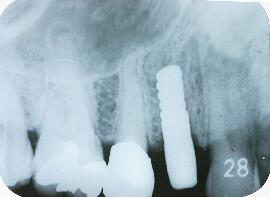

抜歯直後のエックス線写真

抜歯した後の窩洞より太いインプラント体(フィクスチャー)を用意